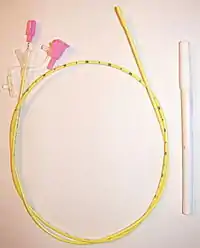

- Dobhoff tube, which is a small bore NG tube with a weight at the end intended to pull it by gravity during insertion. The name "Dobhoff" refers to its inventors, surgeons Dr. Robert Dobbie and Dr. James Hoffmeister, who invented the tube in 1975.[6]

Only smaller diameter (12 Fr or less in adults) nasogastric tubes are appropriate for long-term feeding, so as to avoid irritation and erosion of the nasal mucosa. These tubes often have guidewires to facilitate insertion. If feeding is required for a longer period of time, other options, such as placement of a PEG tube, should be considered.